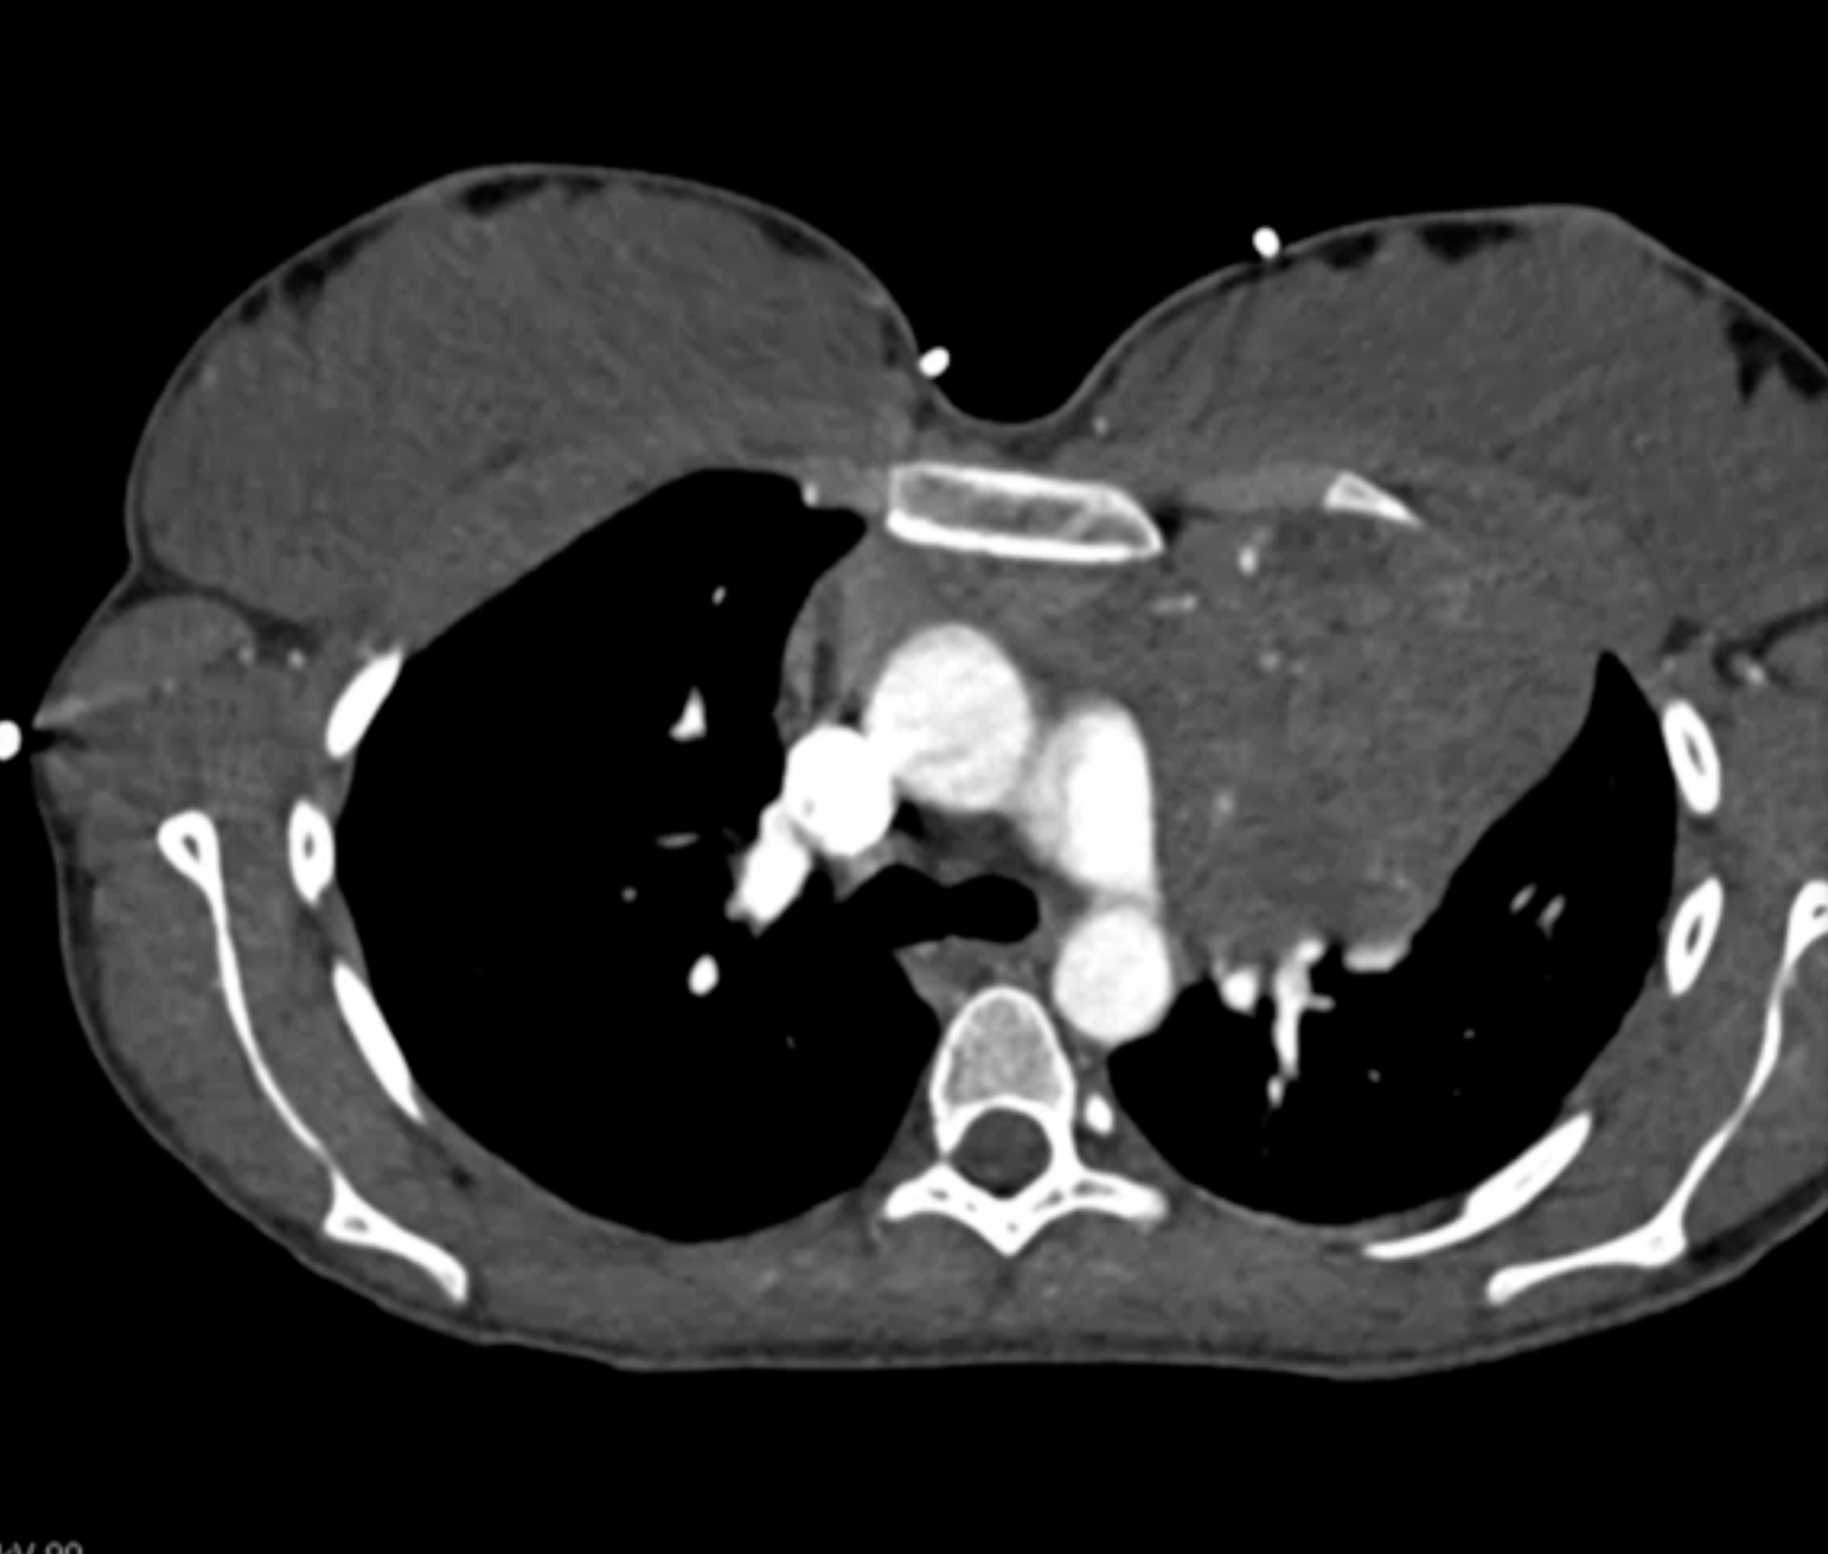

Primary Spindle Cell Carcinoma of the Right Ventricle